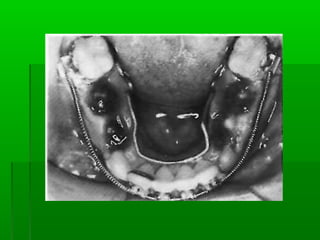

 Blenching TestBlenching Test

lift the upper lip and while it is displaced, looklift the upper lip and while it is displaced, look

for blanching of the soft tissue lingual to andfor blanching of the soft tissue lingual to and

between the central incisors.between the central incisors.

The presence of blenching points to aThe presence of blenching points to a

malposed labial frenum.malposed labial frenum.

DiagnosisDiagnosis  Measure theteeth and compare theirMeasure the teeth and compare their sizes with the averagesizes with the average  Blenching TestBlenching Test lift the upper lip and while it is displaced, looklift the upper lip and while it is displaced, look for blanching of the soft tissue lingual to andfor blanching of the soft tissue lingual to and between the central incisors.between the central incisors. The presence of blenching points to aThe presence of blenching points to a malposed labial frenum.malposed labial frenum.